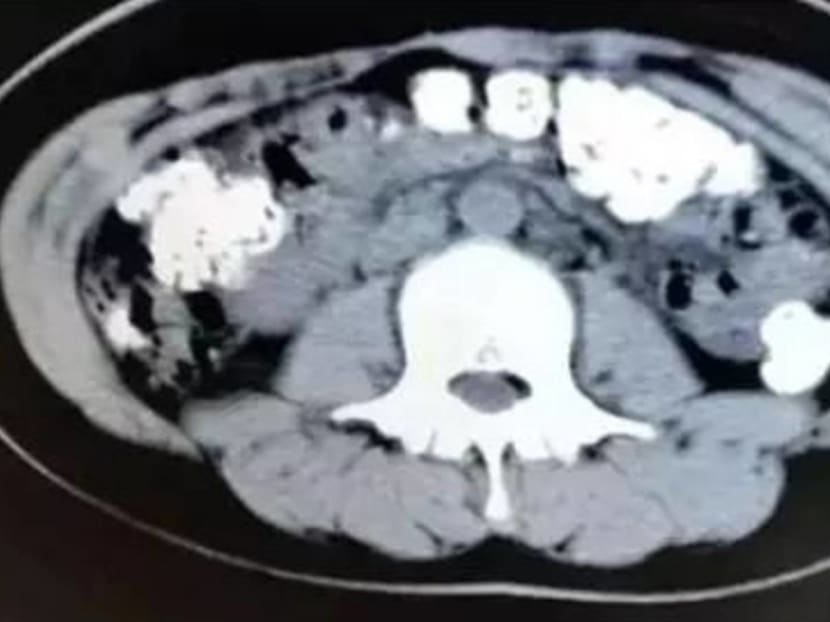

After a CT scan of the girl’s abdominal region, the hospital’s Dr Zhang Louzhen examined the X-ray results and was surprised to find granular shadows filling most of her organs, from the stomach to the colon and anus.

When questioned about what she had eaten recently, the young girl admitted that she had drank a cup of bubble tea five days ago, which led the doctor to conclude that her discomfort was brought about by undigested tapioca pearls, which are commonly found in bubble tea drinks.

The doctor reportedly told Chinese news outlets that it’s highly possible that the girl had been consuming large quantities of bubble tea, which, er, snowballed to her current condition. “That many undigested pearls are usually accumulated by drinking bubble tea over a period,” he was quoted as saying. He also prescribed a laxative to ease the girl’s bowel movements.